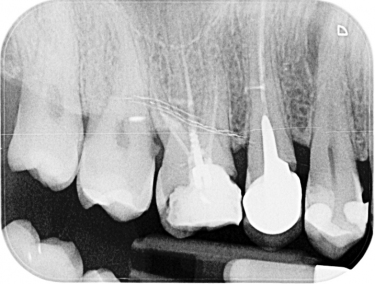

Il termine "devitalizzare" significa letteralmente privare della vita.

Questo trattamento, pertanto, consiste nella rimozione di tutto il tessuto organico albergato dentro il dente al fine di lasciare esclusivamente una struttura estetica e funzionale nella masticazione-occlusione ma facendo cessare qualsiasi patologia infettiva o infiammatoria in corso.

Grazie ad un attento studio diagnostico ricerchiamo prima di tutto la causa del problema e valutiamo tutte le opzioni terapeutiche opportune.

Ci assicuriamo della resistenza strutturale del dente e della sua restaurabilità affinchè il beneficio di questo trattamento sia esteso al lungo termine evitando in questo modo la perdita del dente stesso.